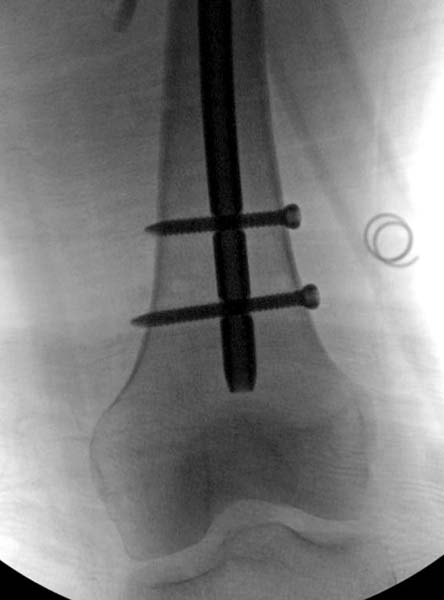

Около 11.00 вечера больная переведена в реанимацию, без сознания, но стабильная.. На третьий день провели стабилизацию перелома бедра антеградным остеосинтезом.

Закрытый БИОС решает множественные проблемы связанные с лечением переломов, но проблема дистальной блокировки без рентгена до сих пор остается нерешенной. Рекламированные производителями приспособления для дистальной блокировки из-за различной кривизны кости не эффективны или стоит очень дорого (Smith&Nephew SureLock). Задержка операции из-за блокировки не всегда удовлетворяет, и многих вынуждает искать альтернативные методы фиксации. С результатами таких действий, остеомиелитом и несращениями, встречаемся в ежедневной жизни..

Для решения проблемы дистальной блокировки компания DigiMed недавно предложила систему блокировки без рентгена. Пока в стране только два набора и только для антеградных гвоздей, но компания работает над созданием устроиства для других гвоздей тоже..

Результат первых случаев показала отсутствие разницы между занятиями на муляжах, а также Workshop и с удивительной точностью вывел латерально над кожей специальное сверло. Дальше по сверлу тонкий направитель и проводится сверление каннюлированным сверлом....